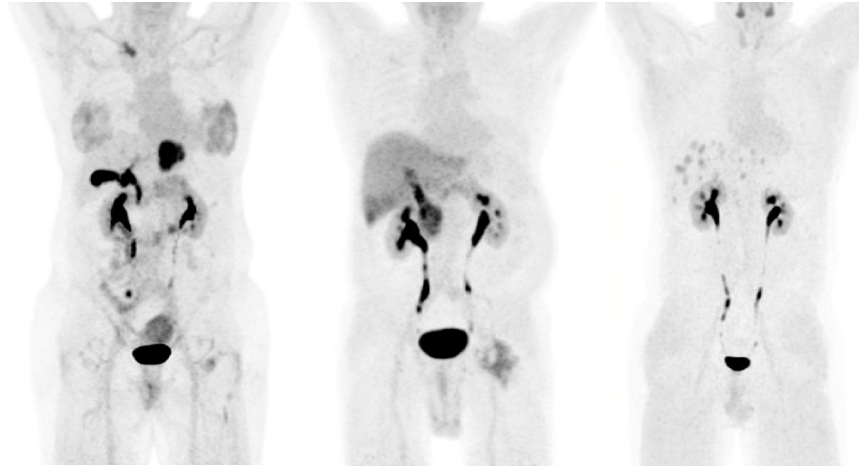

FAP has quickly progressed from proof-of-concept to late-phase clinical development in oncology (with non-oncology indications following soon), gaining momentum toward diagnostic approval. As we approach potential clinical approval, key challenges include healthcare system readiness, sufficient site networks, and prepared readers.

This live round-table discussion brings together experts from industry and academia to examine system readiness across three dimensions: healthcare infrastructure, site networks, and image readers.